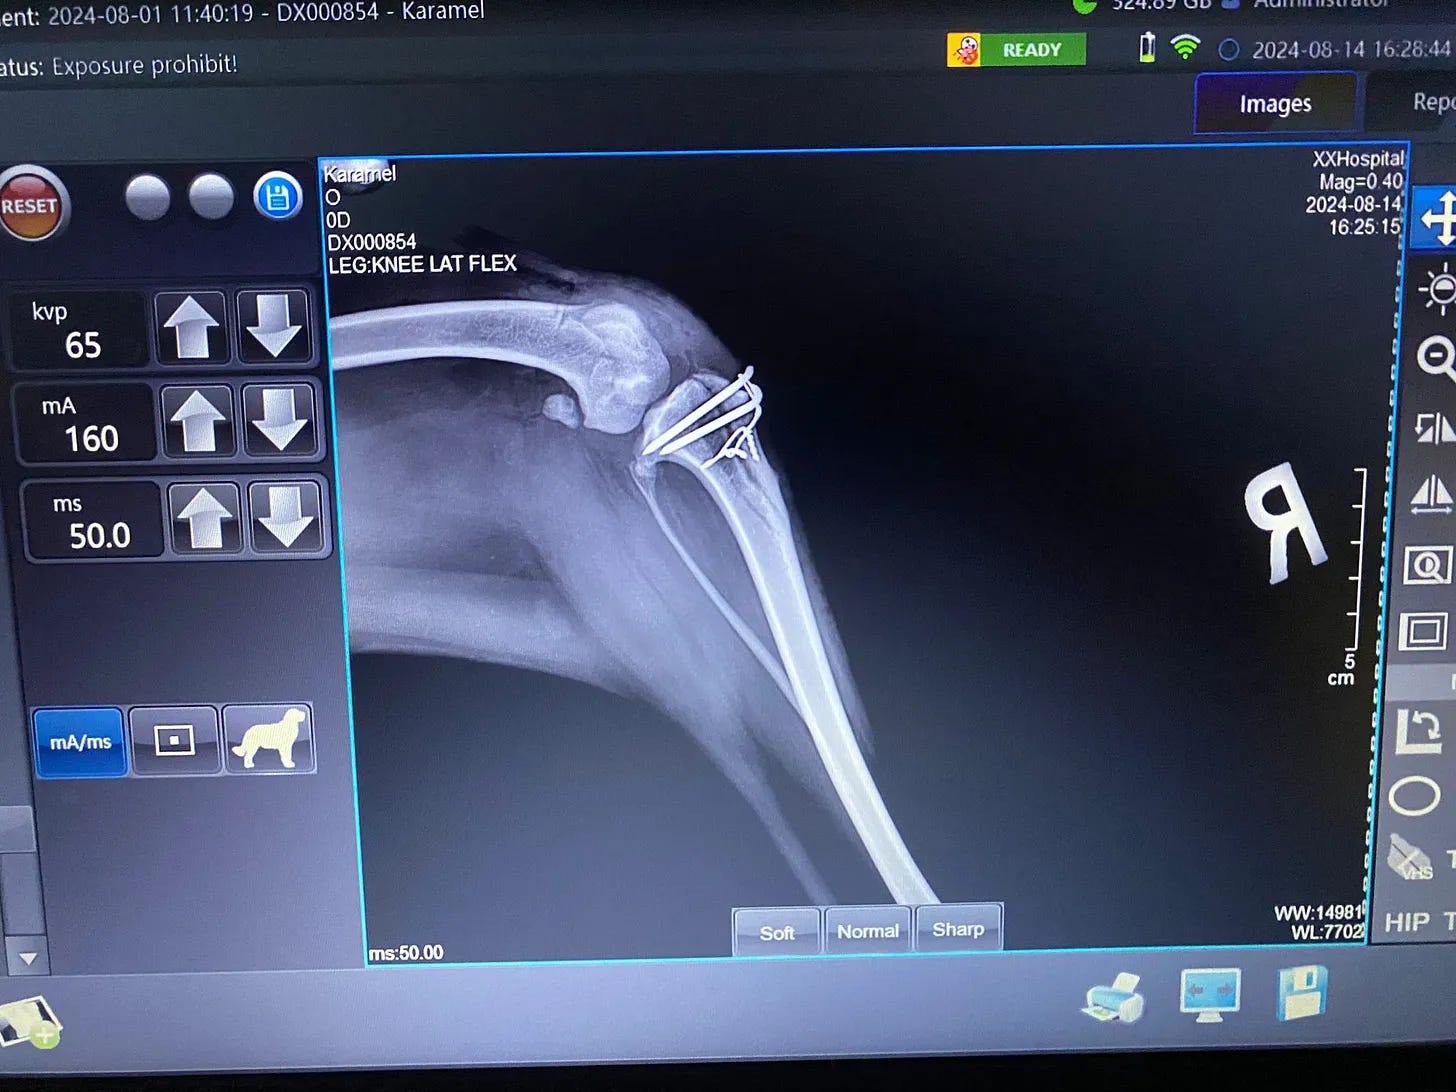

Someone had slammed her back end into the ground with the force of a boot. The trauma forced both her knees sideways.

Under the guidance of a university professor of veterinary medicine, our orthopedic surgeon performed a complex and delicate operation to repair the damage. The surgery itself was a success, and for a brief time, there was hope that she might reclaim some of the life stolen from her.